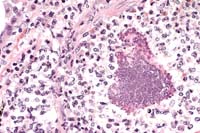

Case 27-3. Heart valve. Fungal hyphae with non-parallel sides are partially surrounded and being phagocytized by multinucleated giant cells which are admixed with fibrin, histiocytes and small lymphocytes. PAS 40X

Contributor's Diagnosis and Comments: Vegetative mural endocarditis of the left atrium caused by a fungus of the Zygomycetes class.

The vegetation contains fibrin, amorphous proteinaceous material, erythrocytes, a mixture of leukocytes, cellular detritus and myriads of fungal hyphae. Several multinucleate giant cells are present in the area of attachment to the endocardium. Fibroplasia is present in that region also. Fungal hyphae are nonseptate, branch irregularly and do not have parallel sides. These are characteristics of the Zygomycetes class, which includes several pathogenic genera such as Absidia, Mucor and Rhizopus spp. Cultures were not attempted. Microscopic granulomas were found adjacent to the major bronchus of one lung. Similar fungal hyphae were present there and we conclude that the lesion in the left atrium developed secondary to the pulmonary infection.

AFIP Diagnosis: Heart: Endocarditis, vegetative, heterophilic and granulomatous, valvular and mural, severe, with focally extensive myocarditis and epicarditis, and numerous fungal hyphae, conure, avian, etiology consistent with a mucoraceous zygomycete.

Conference Note: Conference participants discussed the morphologic differences between Aspergillus sp., common pathogens of birds, and Zygomycetes, which are occasionally seen in immunocompromised or debilitated birds. Aspergillus sp. hyphae are typically 3 to 6 mm wide, septate and branched. Branching is dichotomous and often at acute angles. Typical mucoraceous hyphae vary from 5 to 20 mm wide and branch nondichotomously at right angles. The hyphal walls are thin and often become twisted or folded.